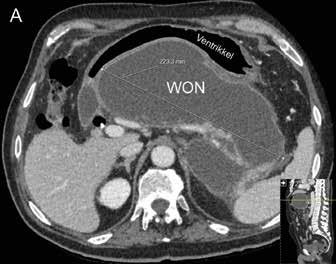

Behandling av walled off nekroser (WON) Akutt pankreatitt har et alvorlig forløp hos ca. 20 % av pasientene med utvikling av pankreatiske og/eller peripankreatiske nekroser (nekrotiserende pankreatitt) og truende multiorgan affeksjon. Disse pasientene kan ha et langtrukkent forløp med uker og måneder på sykehus. Forløpet er typisk 2-faset hvor den første uken (tidlige fase) er preget av systemisk inflammatorisk responssyndrom (SIRS) og organsvikt, etterfulgt av en sen fase (etter 1-2 uker) der komplikasjoner kan oppstå som følge av infeksjon i nekrotisk vev, kompresjon/obstruksjon av gallegang og/eller GI tractus, pseudoaneurismer, lekkasje fra pankreasgang, m.m. I den sene fase vil nekrosene gradvis innkapsles i lokulamenter kjent som

WON, og hos ca. 50 % av pasienten vil disse kreve invasiv behandling. Behandlingen av WON har gjennomgått en revolusjon de senere år hvor man nå ikke intervenerer mer enn nødvendig og så sent som mulig ut fra det kliniske bildet («step-up» strategi). Endoskopisk transmural drenasje har blitt standard behandling og første valg fremfor tradisjonell kirurgisk drenasje. Indikasjoner for endoskopisk drenasje er de samme som for kirurgisk drenasje: mistenkt infiserte nekroser (vanligste indikasjon), obstruksjon/kompresjon av GI tractus/gallegang eller manglende klinisk bedring i senforløpet («failure to thrive»). Som hovedregel må man vente til nekrosene er demarkert (synlig kapsel på CT) og man har en etablert WON, det vil si minst 3-4 uker eller senere ut i forløpet. Gode CT bilder og/eller MR bilder (helst < 1 uke gamle) er viktig for å få informasjon om størrelse og utbredelse av WON, andel nekroser i kaviteten, avstand fra ventrikkel (duodenum), pseudoaneurismer og eventuelle større blodkar (f.eks. miltkarene) i relasjon til kaviteten samt tilstedeværelse av gastriske varicer, både med tanke på risiko i relasjon til prosedyren og risiko for et mer langvarig forløp hvor det bl.a. kan bli behov for nekrosektomi. Endoskopisk drenasje bør bare gjøres dersom multidisiplinært team er tilgjengelig (endoskopør, gastrokirurg, intervensjonsradiolog og anestesiolog) både med tanke på indikasjonsstilling og håndtering av eventuelle komplikasjoner i forløpet.

Endoskopisk behandling er som nevnt førstelinjebehandling og bør uansett forsøkes først dersom teknisk mulig da ekstern drenasje av væskefasen og eventuell tilførsel av luft i WON kan vanskeliggjøre senere endoskopisk behandling. Tilhelingstid er normalt 4-6 uker avhengig av størrelse, utbredelse og andel faste nekroser i kaviteten, men kan hos enkelte pasienter være betydelig lenger. Stenten (LAMS) fjernes når kaviteten er borte (Fig 2).

Fig 2: CT bilder fra pasient med nekrotiserende pankreatitt og behandlingstrengende WON før drenasje (A) og 4 uker etter (B) innleggelse av LAMS (pil).